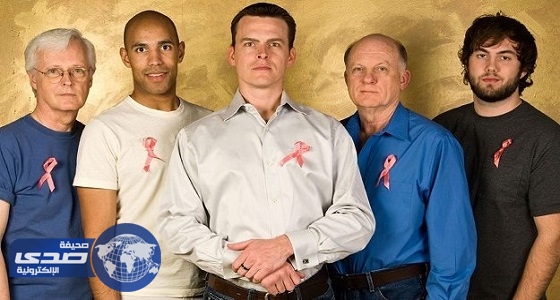

«سرطان الثدي» يصيب الرجال أيضاً وإليك أعراضه